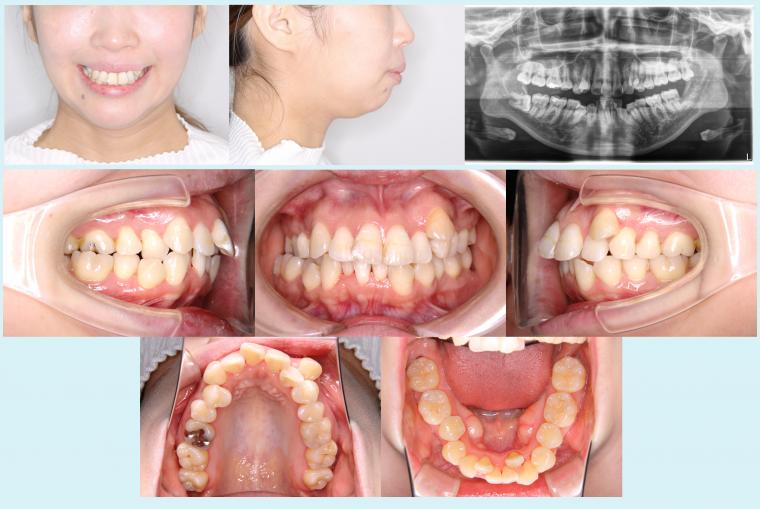

症例集の掲載をスタートいたしました。 - 2022.12.12